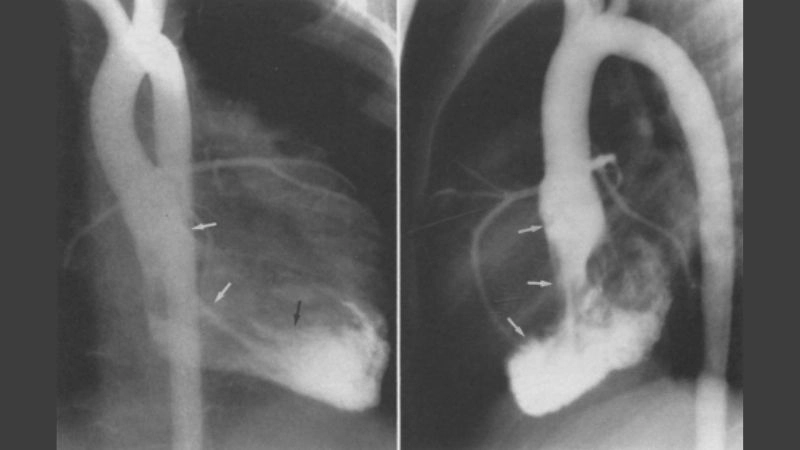

Images visual examples of cardiac fibroma

Cardiac fibroma is a rare, benign tumor of the heart composed mainly of fibrous tissue. It often develops in children and may cause symptoms related to heart rhythm and pumping function.